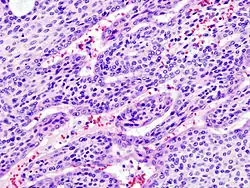

![]() Adenoma pleomórfico con epitelio mixto (izq) y componentes celulares mesenquimatosos (der). Estos últimos exhiben apariencia mixofibroso y cierta diferenciación condromatosa. | ||

Bajo el microscopio, tienen una apariencia altamente variable, incluso dentro de un mismo tumor. Clásicamente, es un tumor bifásico y se caracteriza por tener una mezcla de epitelio poligonal y elementos mioepiteliales de forma de huso en un trasfondo de estroma muy variable que puede ser mucoide, mixoide, cartilaginoso o hialino.[1] Los elementos epiteliales pueden acomodarse en forma de estructuras ductales, o bien en forma laminar, agrupados o en filamentos que se entrelazan. Las células que conforman el epitelio son de dos tipos, luminales (epiteliales) y no-luminales (mesenquimatosos) y pueden también ser poligonales, laminares o estrellados (por ello el término pleomórficos). Puede haber presentes áreas de metaplasia escamosa y perlas epiteliales.

El tumor no está envuelto, pero está por lo general rodeado de una seudo-cápsula de grosor variable. El tumor se extiende en sus dimensiones a velocidades variables, entrando en el parénquima glandular normal, formando un frente de forma de dedo, aunque ésta variación no implica una transformación maligna.